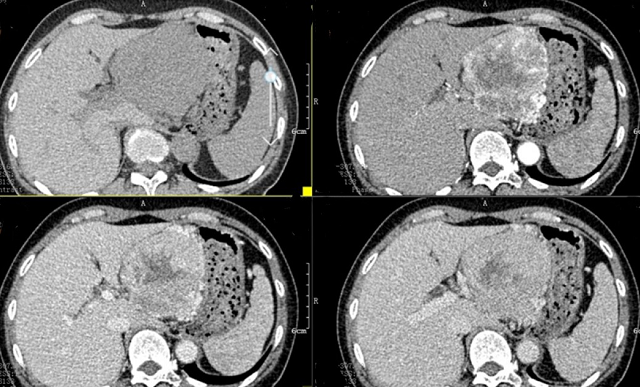

入院后,根據(jù)王女士病情,曹利平教授及其團(tuán)隊(duì)為她制定一套詳盡的術(shù)前檢查和治療方案。首先,安排做上腹部增強(qiáng)CT,并建議其先穿刺活檢明確病理。

“CT表現(xiàn)符合胰腺神經(jīng)內(nèi)分泌腫瘤,穿刺也證實(shí)無誤,但是瘤體實(shí)在太大,直徑約12cm左右,腹腔內(nèi)的門靜脈、腸系膜上靜脈、脾靜脈以及腹腔干這些重要血管統(tǒng)統(tǒng)包繞進(jìn)去了,且與周圍結(jié)腸系膜也有累及。”

曹利平教授帶著團(tuán)隊(duì)成員逐一分析,隱藏在瘤體附近的血管就像埋在炸彈旁的導(dǎo)火索,稍有不慎,便會(huì)引爆這顆瘤體炸彈,要想把腫瘤完整切除,更是難上加難。